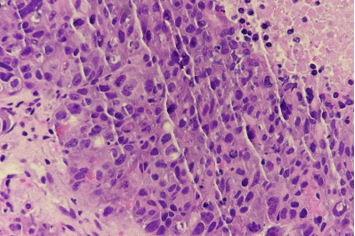

Figure 1. GATA3 immunohistochemical stain highlights in epithelial tumors.

Malignant epithelial tumors with trophoblastic differentiation are rare in men. It would be appropriate to consider these tumors in the context of male choriocarcinoma, which is also a rare entity [1,2]. Although the basic treatment approach is similar to non seminomatous germ cell tumors, the prognosis is almost always much worse [3]. Beta-HCG-secreting tumors should be considered in the differential diagnosis of the young to middle-aged male patient as shown in Figure 2.

XXXXXX

Figure 2. Tumor cells appeared to show syncytiotrophoblastic morphology.